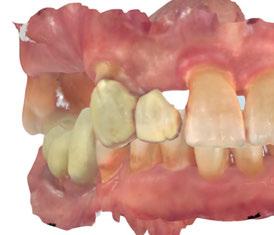

-Registros fotográficos intra y extraorales (Figura 1 a-c).

A partir del estudio radiológico y de las imágenes fotográficas podemos observar edentulismo de 17, 15, 14, 12,

Figura 1a. Foto intraoral frontal inicial.

Figura 1b. Foto intraoral lateral izquierda inicial.

Figura 1c. Foto intraoral lateral derecha inicial.

25, 26, 28, 37, 38, 47 y 48. Presentaba corona desajustada en 13 con extensión en 12, implantes en 35-36, 45-46, con coronas ferulizadas en 35-36, 45-46, y dientes anteriores superiores con enfermedad periodontal Grado IV.

2. Exploración de tejidos blandos

El paciente presentaba biotipo periodontal grueso, con márgenes asimétricos, con recesiones gingivales a nivel de 11 y 13 y pérdida de tejidos blandos interproximales.

3. Exploración de tejidos duros

En la exploración radiográfica (OPG, CBCT) observamos la existencia de pérdida ósea interproximal, lesión apical a nivel de la raíz mesial del 27 y el cordal del primer cuadrante incluido y neumatización sinusal del primer y segundo cuadrante.

En el CBCT observamos pérdida ósea posterior superior debida a la neumatización de los senos maxilares izquierdo y derecho. También podemos observar disponibilidad ósea apical suficiente en dientes antero-superiores para la realización de una Implantología inmediata y corticales vestibulares y palatinas conservadas.